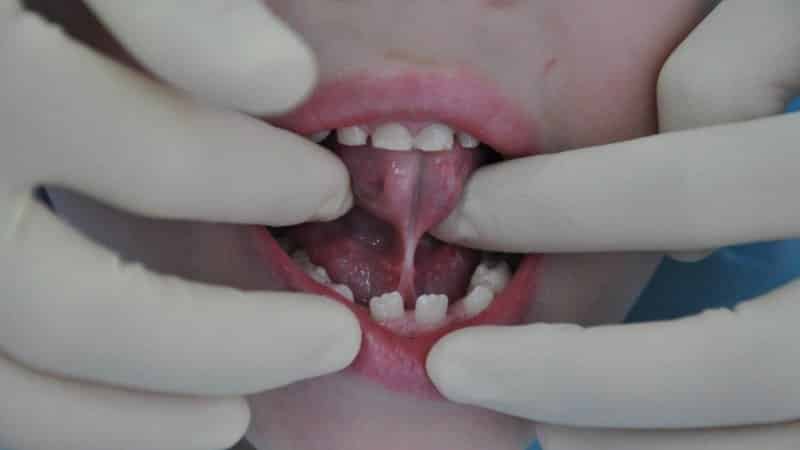

У детей может наблюдаться как полная, так и частичная короткая уздечка языка. В первом случае это приводит к ограничению подвижности языка, и при осмотре можно заметить, как язычок сворачивается в трубочку с обеих сторон. При частичной короткой уздечке присутствует тонкая пленочка, в которой отсутствуют нервные окончания. Родители могут ознакомиться с изображениями полной короткой уздечки у новорожденных, чтобы определить наличие признаков у своего малыша.

Сравнивая фотографии короткой уздечки языка у новорожденных, родители могут лучше понять аномалию и сопоставить с состоянием ротовой полости своего ребенка.

Дети постарше, испытывающие трудности с произношением шипящих звуков и буквы Р, также должны пройти обследование на наличие короткой уздечки. Ее можно определить визуально. В некоторых случаях уздечка прикреплена на самом кончике языка, что ограничивает его движение. При нормальном креплении уздечка может быть слишком короткой, что затрудняет ребенку возможность дотянуться языком до нижней губы, облизывать губы или проводить по верхним деснам с внутренней стороны. У таких детей часто слышны непроизвольные щелчки и клацающие звуки. Когда ребенок высовывает язык, он принимает горбатую форму или сворачивается, как желобок. Если попросить его издать клацающие звуки, он не сможет это сделать. В возрасте пяти лет длина уздечки в растянутом состоянии в среднем составляет 0,8 см, и при подъеме языка не должно быть раздвоения, напоминающего сердечко.

Можно ознакомиться с фотографиями, на которых видно, как выглядит короткая уздечка языка у ребенка до и после операции. После вмешательства у малыша постепенно исчезают анатомические дефекты, улучшается дыхание, а также наблюдается значительное увеличение веса. Повышается вероятность предотвращения неправильного прикуса и устранения проблем с речью.